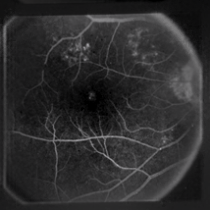

Figure 7: Three FA fundus images with symptom of GA and corresponding generated images. (a), (b), (c) Original images. (d), (e), (f) Generated images.

Furthermore, generated images from FA images are presented in Fig. 6 and Fig. 7. Results in the images are nearly identical to the original images, because original networks are applied to stylize color images. However, six generated images contain more concise features than the original ones, which helps ophthalmologists make better judgments. Therefore, this style transferring networks can fulfill edge sharpening and enhancement of contrast. No matter which kinds of images are generated, advanced features in new disease images still exist. Furthermore, analyses of image performance by EyeNet and CAMs for prediction are presented in a later section.

4.3 Style Transferring Neural Networks

Style transferring neural network in [16] was modified to generate new disease images. This network adopts layers from ”conv1 1” to ”conv4 1” in pre-trained VGG-19 [24] network for the encoder, whose weights are provided by ImageNet-pretrained weights. What’s more, multi-level stylization strategy proposed in [16] is applied to optimize the VGG features in different layers. Input images are three CFP images and three FA images as style images shown in Fig. 2 and 5. Six CFP images with three drusen and three GA images in Fig. 3 and Fig. 4. Also, FA images are applied to generate new images in Fig. 6 and Fig. 7. For CFP images, six images are shown in Fig. 3 and in Fig. 4. In Fig. 3, generated images contain round, discrete yellow-white dots, which are the symptom of drusen. In the same way, in Fig. 4, well-demarcated areas appear on the three images. Therefore, style transferring can generate new retinal symptom images.